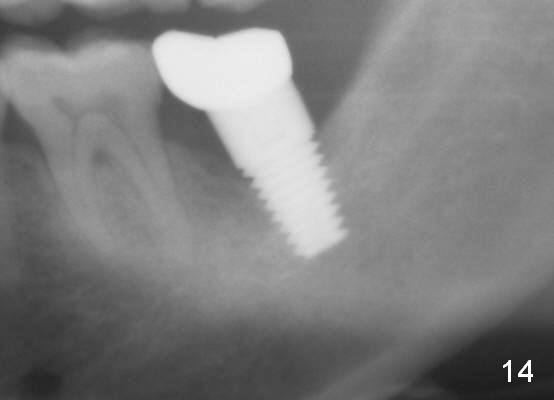

The lower left 2nd molar of a 45-year-old lady has perio-endo disease (Fig.1). The patient is not only very nervous, but also active in gag reflex. It is difficult to take good preop PA (Fig.1 *: ). Root canal therapy is performed. A relatively good PA is taken 1 year postop, again due to gap reflex (Fig.2). The tooth is still nonsalvageable (Fig.3). The last PA is taken 3.5 years before extraction and immediate implant. Infiltration anesthesia is administrated first. The patient experiences pain during early stage of osteotomy, but she does not report readily. Block anesthesia is added. Intraop PAs are taken with difficulty (Fig.4,5 with #1 sensor; 5 mm tap in place). Invasion of the inferior alveolar canal is not noted (Fig.5 dashed line). Oozing is a little more than expected. This is ignored. A 7x14 mm tapered implant is placed; the upper border of the inferior alveolar canal is not intact (Fig.6). Paresthesia area is defined next day (Fig.7). The implant is reversed for a few turns. Paresthesia area is reduced 19 days later (Fig.8). The implant is not stable. Follow up PAs are taken with difficulty (Fig.9-11). It appears that a shorter cylindrical implant is more appropriate for this case (Fig.11). The implant is stabilized with splinting with questionable result (Fig.12).

There is bone growth in the mesial socket 1 year postop (Fig.14, as compared to Fig.13 (immediately postop, before back up). Mild paresthesia remains 2 years postop.